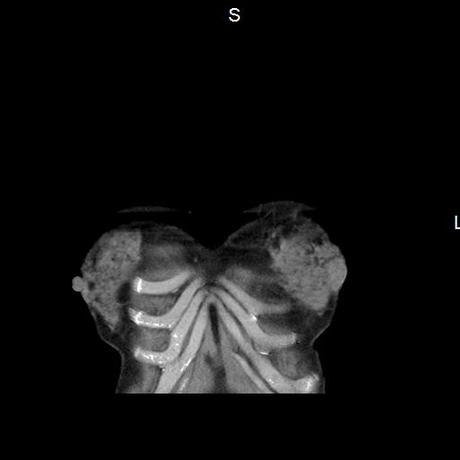

El parénquima pulmonar con areas parcheadas difusas en vidrio despulido combinadas con otras areas hipodensas de baja atenuación debidas a atrapamiento aéreo y engrosamiento intersticial y zonas de fibrosis de predominio en lóbulos medios e inferiores de ambos pulmones.

- LOS HALLAZGOS PUEDEN ESTAR EN RELACIÓN A NEUMOPATIA INTERSTICIAL PROBABLE ETIOLOGIA HIPERSENSITIVA VS AUTOINMUNE/BACTERIANA/FUNGICA.